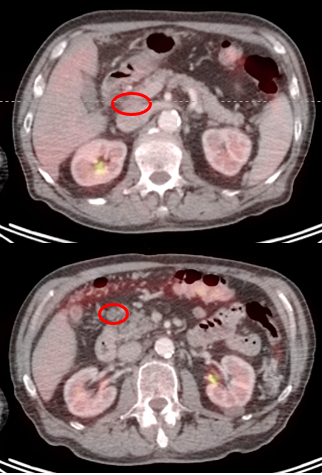

ПЭТ/КТ: март 2024: выраженная положительная динамика. Последующие исследования показали полный регресс опухоли